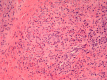

Eosinophilic angiocentric fibrosis (EAF) is an exceedingly rare and potentially disfiguring and obstructing benign lesion involving the upper airways. We report two cases of EAF originating from the nasal cavity in a 31-year-old female and a 58-year-old male exhibiting nasal obstructive symptoms, with imaging features and histopathology characteristic of EAF. Surgical excision was performed on one patient with a disfiguring nasal mass at a tertiary referral rhinology practice within a university centre. Summarized are the relevant clinical issues to increase awareness of this disease. The slow progression and rarity of the disease has previously resulted in diagnostic difficulty. We review the limited current literature surrounding the clinical features and treatment options for this progressive and potentially morbid condition. These cases reinforce that, while rare, inflammatory and fibrosing lesions in general should still be considered as part of the differential diagnosis in patients presenting with obstructive lesions in the sinonasal tract.